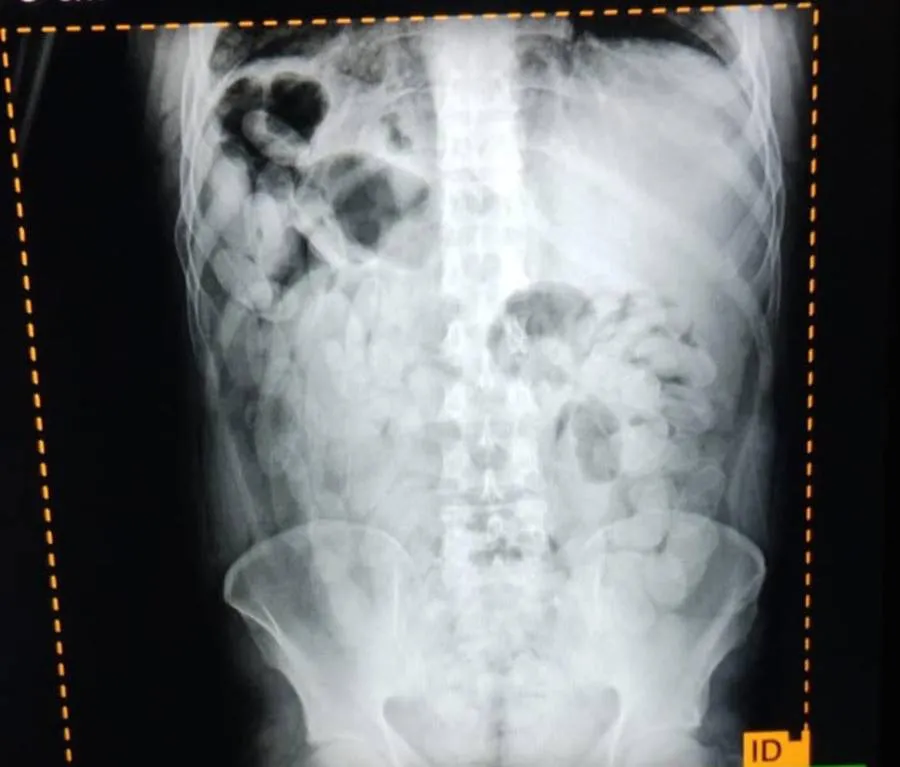

Ante las altas posibilidades de estar frente a la modalidad de traslado de estupefacientes denominada "capsulero" y para preservar la salud de las personas, se solicitó asistencia de emergencia y el traslado al Nosocomio local, en donde mediante placas radiográficas pudieron confirmar la presencia de capsulas.

Luego, los involucrados evacuaron 180 capsulas que sometidas a la prueba de campo Narcotest dieron resultado positivo para cocaína con un peso total de 2 kilos 102 gramos.